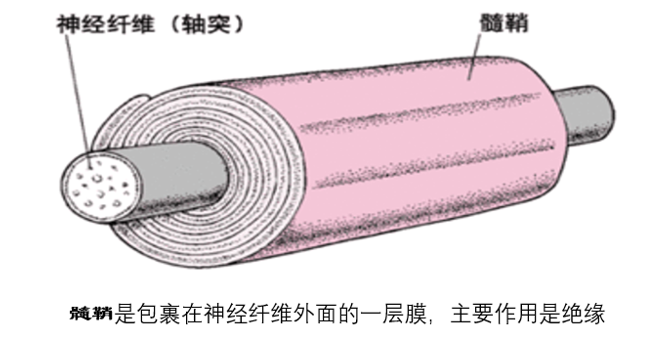

髓鞘是包裹在神经纤维外的细胞膜,通俗一点讲有点类似于包裹在电线外

图片尺寸892x606

以维持有髓鞘的神经纤维功能完整,维生素b12缺乏时可出现神经系统症状

参与形成中枢神经系统有髓神经纤维的髓鞘.